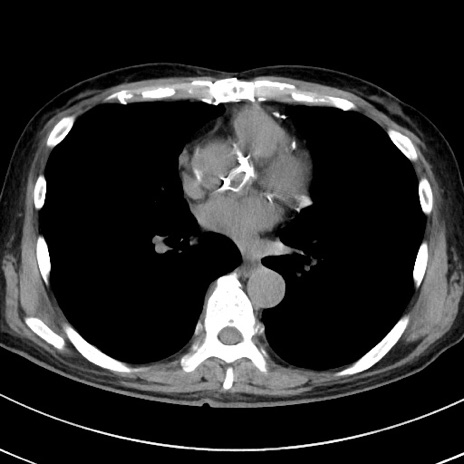

症例38(横断像)

【症例】70歳代 男性

【主訴】腹痛・嘔吐

【現病歴】昨晩より、嘔吐・腹痛あり。今朝になっても嘔吐あり。来院。

【既往歴】心臓バイパス手術、開腹胆摘、腸閉塞

【身体所見】BP 107/71mmHg、HR 116/min、腹部:平坦、軟、下腹部に軽度圧痛あり。反跳痛なし。

【データ】WBC 15100、CRP 0.32